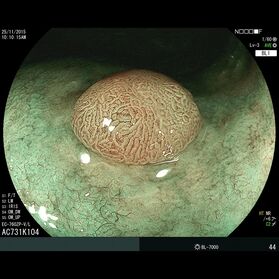

Die Darmspiegelung ist der uneingeschränkte Goldstandard für die Diagnostik und Vorsorge sämtlicher Erkrankungen des Dickdarms und des untersten Dünndarms. Die hochauflösende Bildqualität (High Definition) unserer modernen Videokoloskope ermöglicht eine zuverlässige Einordnung nahezu sämtlicher entzündlicher oder geschwulstiger Veränderungen der Dickdarmschleimhaut.

Die Darmspiegelung hilft, dass Darmkrebs gar nicht erst entstehen kann. Denn während der Untersuchung werden auch Polypen entfernt, aus denen sich der Darmkrebs in der Regel entwickelt. Von allen Maßnahmen zur Früherkennung dieser Polypen besitzt die Koloskopie die höchste Empfindlichkeit. Sie weist kleinste Polypen, aber auch Darmkrebs nach, der noch keinerlei Symptome macht. Die Abtragung dieser Polypen erfolgt direkt, wenn sie entdeckt werden. Das geschieht völlig schmerzfrei. Durch die Abtragung der Polypen kann die Entstehung von Darmkrebs effektiv verhindert und die krebsbedingte Sterblichkeit gesenkt werden.